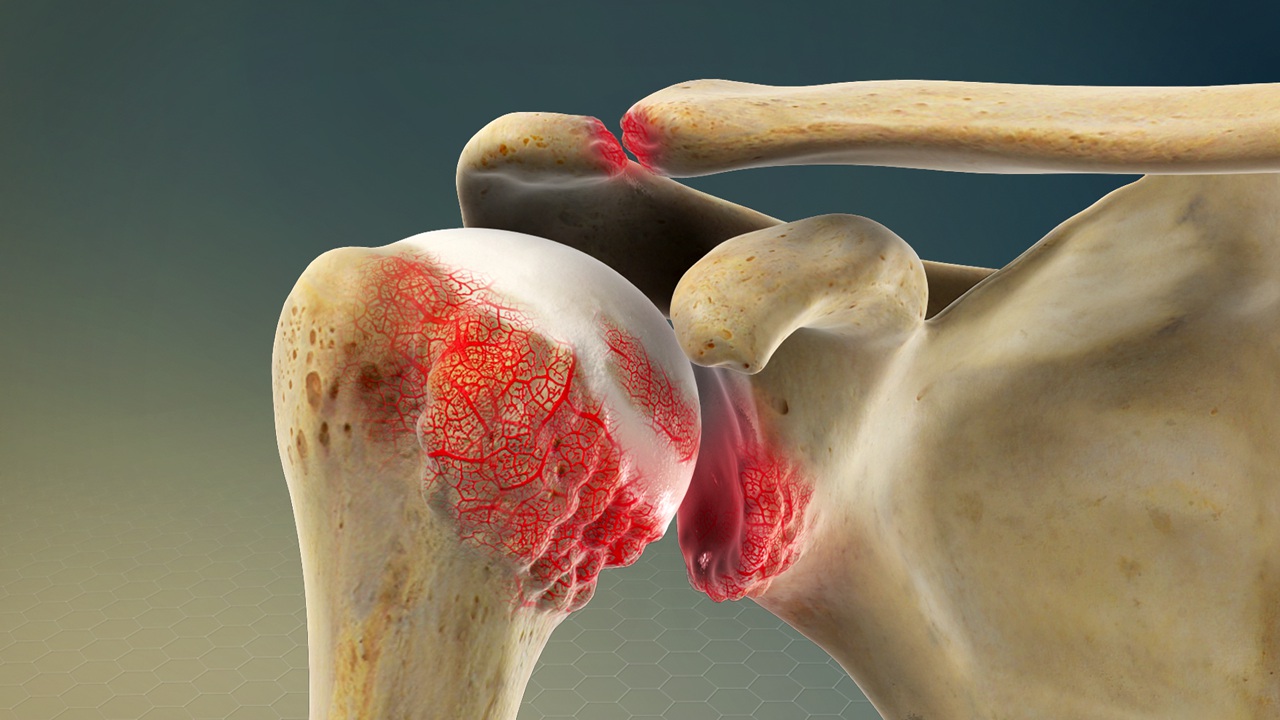

Shoulder joint osteoarthritis

Osteoarthritis is a degenerative condition of the joints seen in the elderly people and is characterised by loss